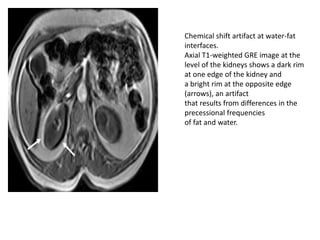

Chemical shift artifact at water-fat

interfaces.

Axial T1-weighted GRE image at the

level of the kidneys shows a dark rim

at one edge of the kidney and

a bright rim at the opposite edge

(arrows), an artifact

that results from differences in the

precessional frequencies

of fat and water.